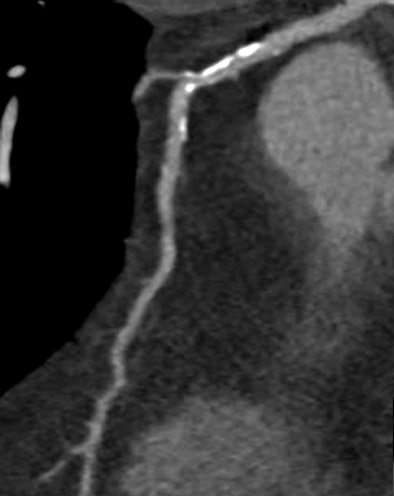

![]() |

| Significant calcified stenosis of the RCA and LAD, both correctly diagnosed with dual-source CT coronary angiography; and nonsignificant stenosis of the LCX. |